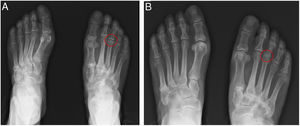

Non-weightbearing (Fig. 1A) and weightbearing (Fig. 1B) anteroposterior radiographs demonstrated a Freiberg disease in a 78-year-old female patient with forefoot chronic pain, swelling and restricted motion of the right third metatarsophalangeal joint. Laboratory results revealed normal inflammatory parameters. Radiographs images showed reduction in the height of the articular interline (Fig. 1A), subchondral sclerosis and flattening (Fig. 1B) of right third metatarsophalangeal head compatible with an avascular necrosis of right third metatarsal head. The patient was improved with daily activity and shoe wear modifications combined with an oral nonsteroidal anti-inflammatory drug. Freiberg disease is a rare clinical condition characterized by avascular necrosis of metatarsal head, most commonly the second metatarsal. The etiology of this condition is multifactorial, involving traumatic causes, vascular compromise and systemic disorders such as systemic lupus erythematosus. The differential diagnostic based on clinical presentation and radiograph findings is crucial and include stress fracture, neuroma, rheumatoid arthritis and gout. Conservative management, namely rest, activity and/or shoes modifications and analgesia aims to control pain and prevent progression. However, when these interventions are ineffective, surgical treatment may be indicated.